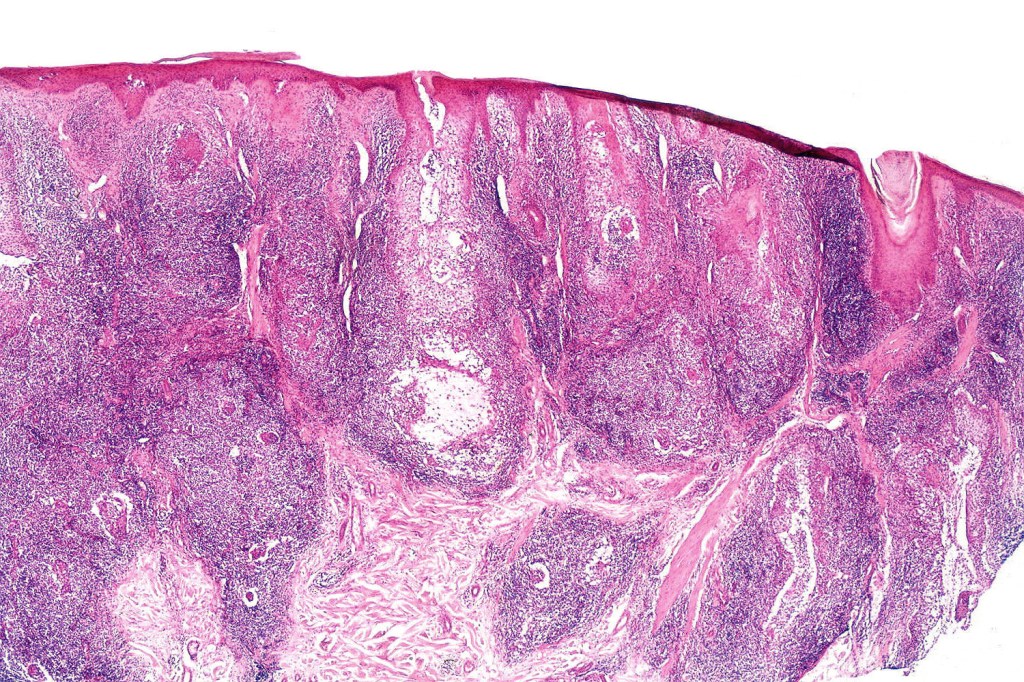

Histological features

•Epidermal involvement often absent

•Follicular infiltration by atypical lymphocytes & Sézary cells

•+/- mucinosis